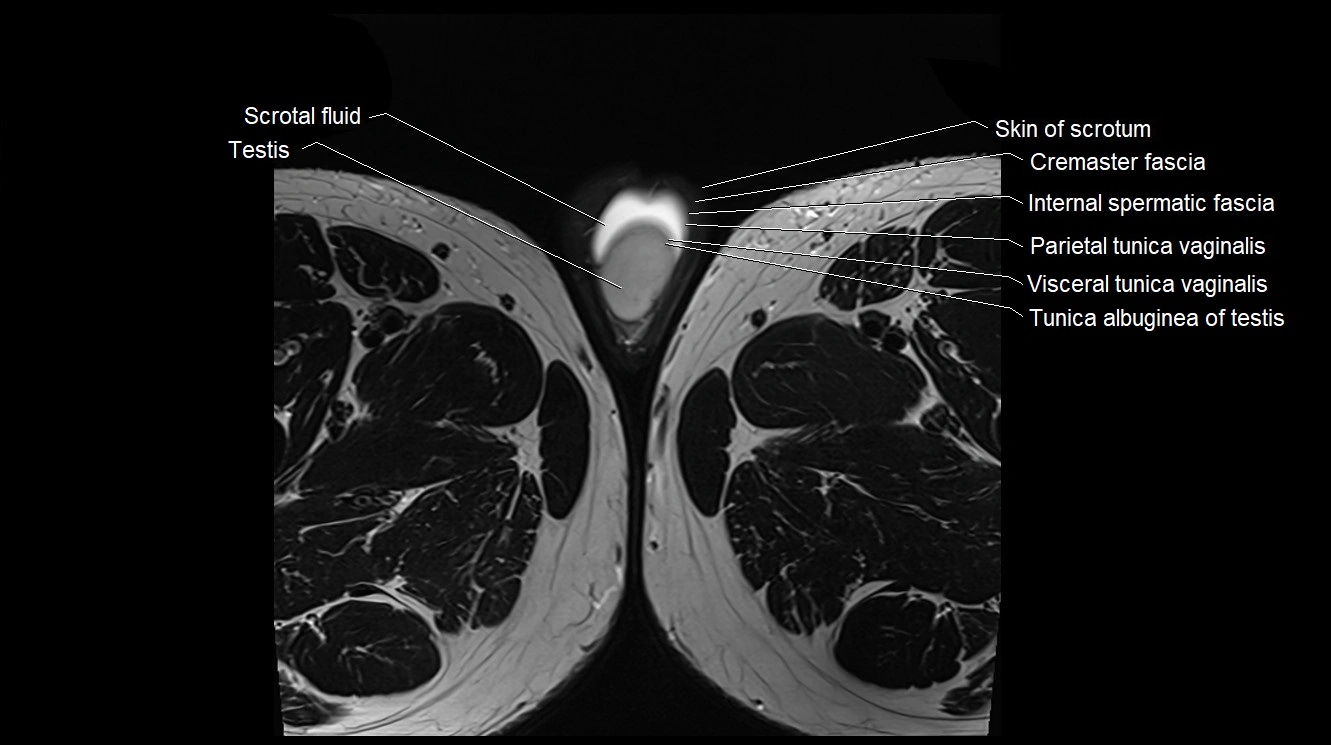

- Cremaster fascia

- Internal spermatic fascia

- Parietal tunica vaginalis

- Scrotal fluid

- Skin of scrotum

- Testis

- Tunica albuginea of testis

- Visceral tunica vaginalis